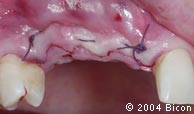

31. | 缝合。 |